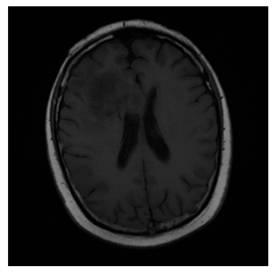

ACRIN-DSC-MR-Brain database (available at: https://wiki.cancerimagingarchive.net/pages/viewpage.action?pageId=50135264 (accessed on 4 November 2021))

ACRIN-DSC-MR-Brain database contains MRI-type and CT-type brain medical images. Some samples are shown in Figure 12b.

Figure 12. Sampled images in the tested benchmark databases: (a) Breast-MRI-NACT-Pilot (breast), (b) ACRIN-DSC-MR-Brain (brain), (c) NIH (chest), (d) Lung-PET-CT-Dx (lung), (e) Prostate-MRI (prostate), and (f) Other grayscale standard images.